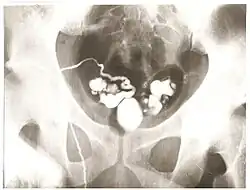

Vasography is an X-ray study of the vas deferens to see if there is blockage, oftentimes in the context of male infertility.[1] An incision is made in the scrotum, contrast is injected in the vas deferens, and X-rays are taken from different angles.[1] Thus, it is an invasive procedure and carries risk of iatrogenic scarring and obstruction of the vas.[2] Vasography has traditionally been considered the gold standard imaging modality for evaluating the seminal tract patency.[3]